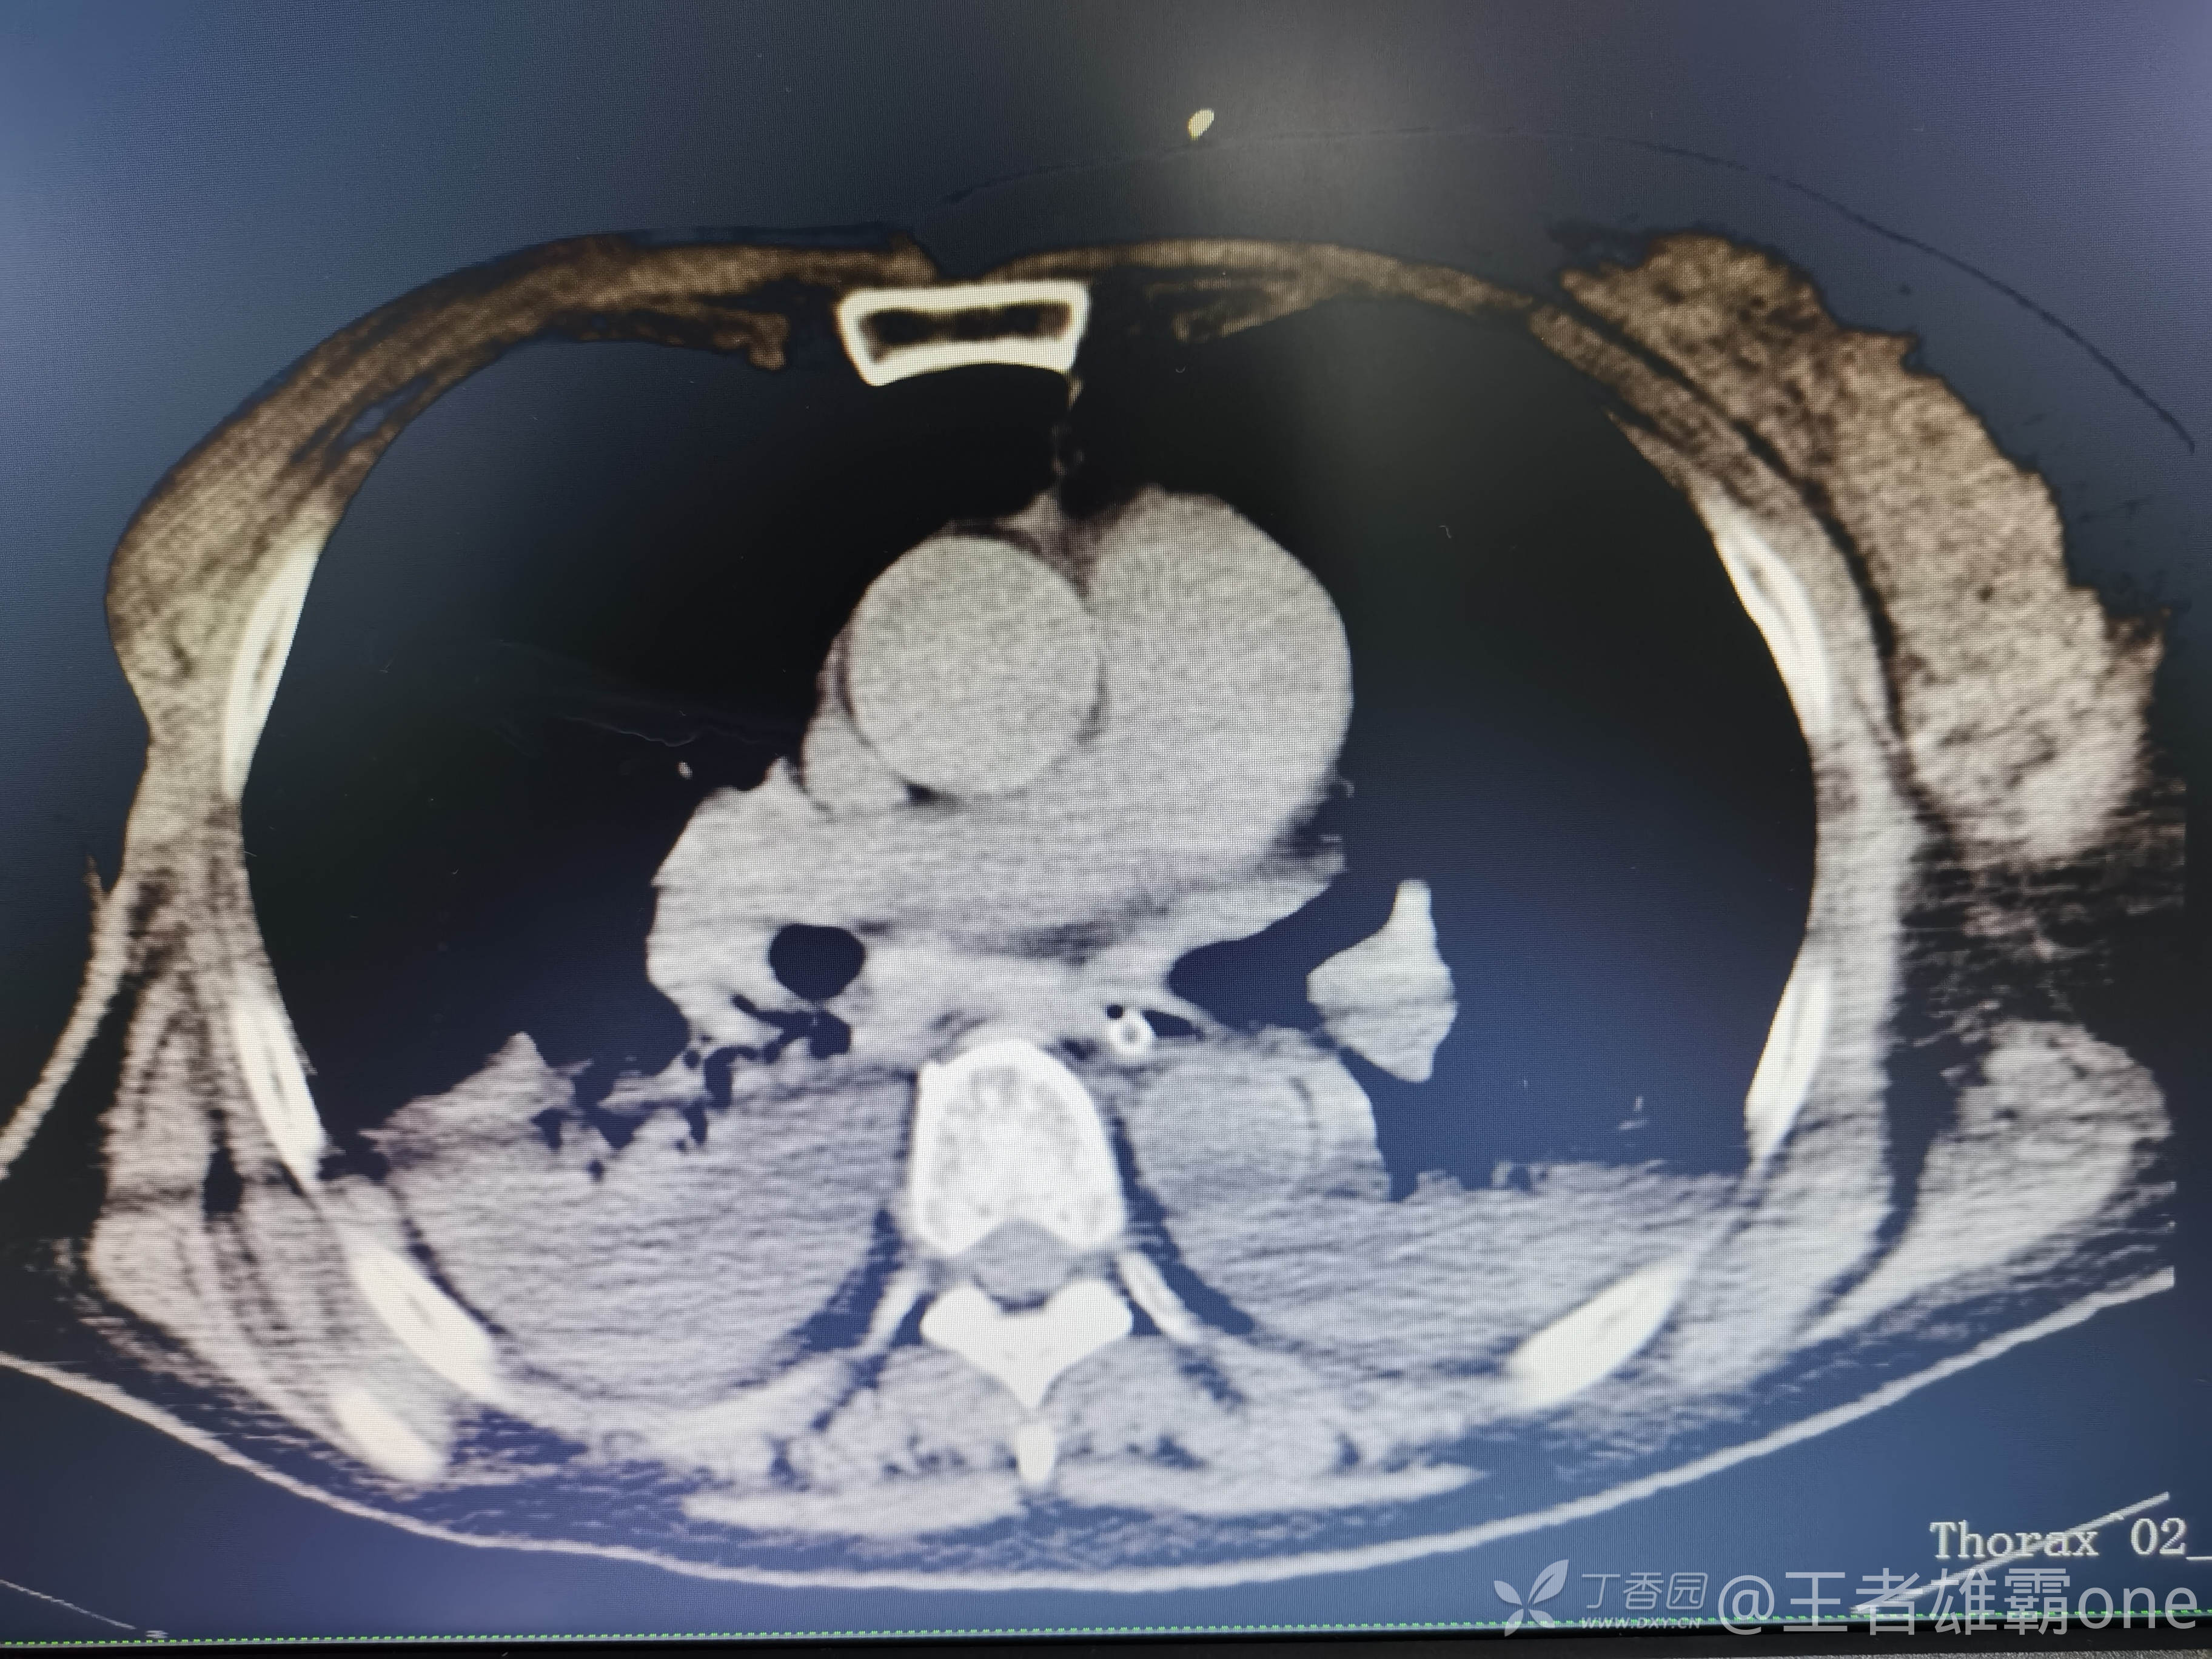

西门开心 推荐63岁女性,因车祸致短暂神志不清、多处疼痛4h入院。简单病史:伤后送至医院急诊就诊。完善头胸腹CT等检查,完善新冠核酸、血常规等化验。血常规提示血红蛋白62g/L。头颅CT提示未见明显外伤性改变。胸腹部CT视频见下:

早上复查血常规:血红蛋白100g/L,白细胞11.1×109/L,血小板29×109/L。凝血功能:APTT37.9s,纤维蛋白原3.01g/L,凝血酶时间18.6s,D二聚体21530ug/L。生化:白蛋白36.2g/L,胆红素指标正常,谷丙56U/L,总胆红素38mmol/L,直接胆红素12.1mmol/L,谷草57U/L,肌酐91.1ummol/L,尿素13.97mmol/L,超敏C反应蛋白142.1mg/L。降钙素原17.70ng/ml。脑钠肽前体2164pg/ml。复查胸部CT: